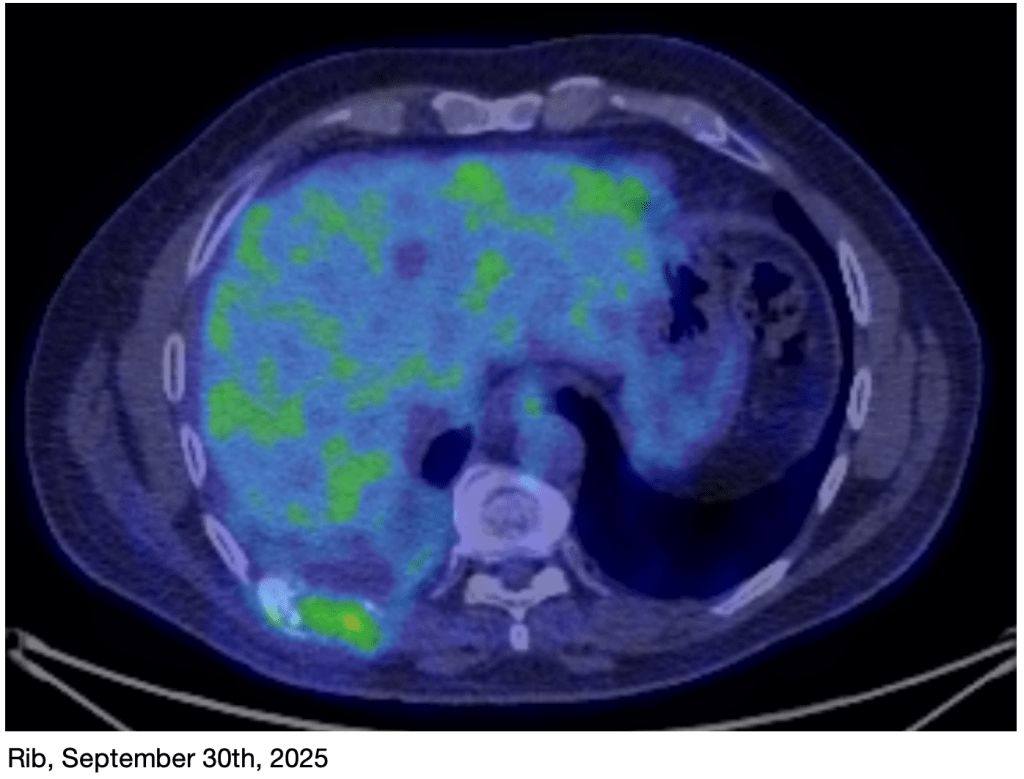

I had another PET scan on Tuesday of this week. The results are very encouraging!

We will meet with my oncologist on Thursday to discuss the results and plan next steps. I don’t think we will actually deviate from the current plan.